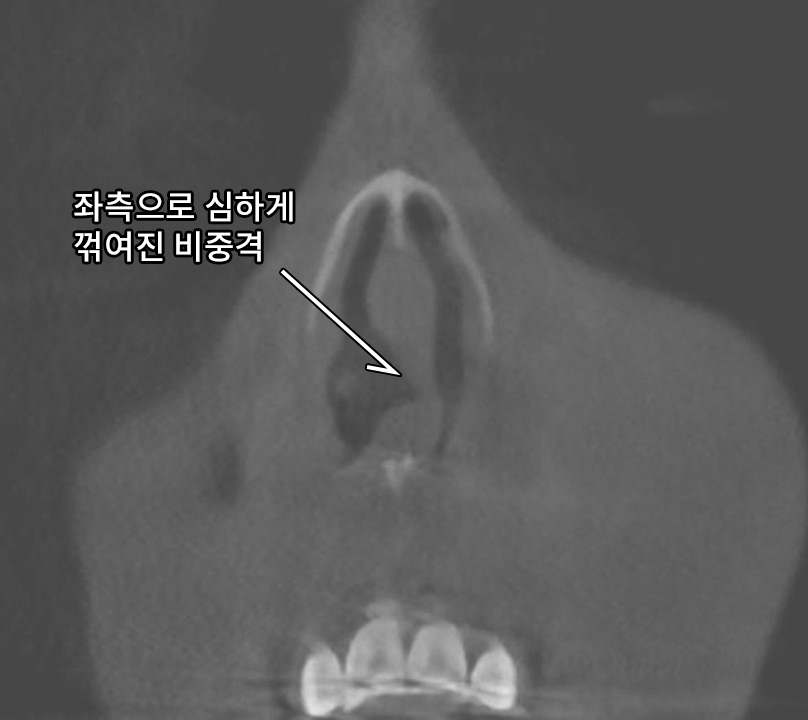

Trussed Structure Using ‘LOCK’ Technique for Septal Reconstruction in Contracted Nose Septal reconstruction is a crucial procedure in correcting a

Short Nose Correction: A Comprehensive Guide Short nose, also known as hypoplastic nose, is a common aesthetic concern among individuals